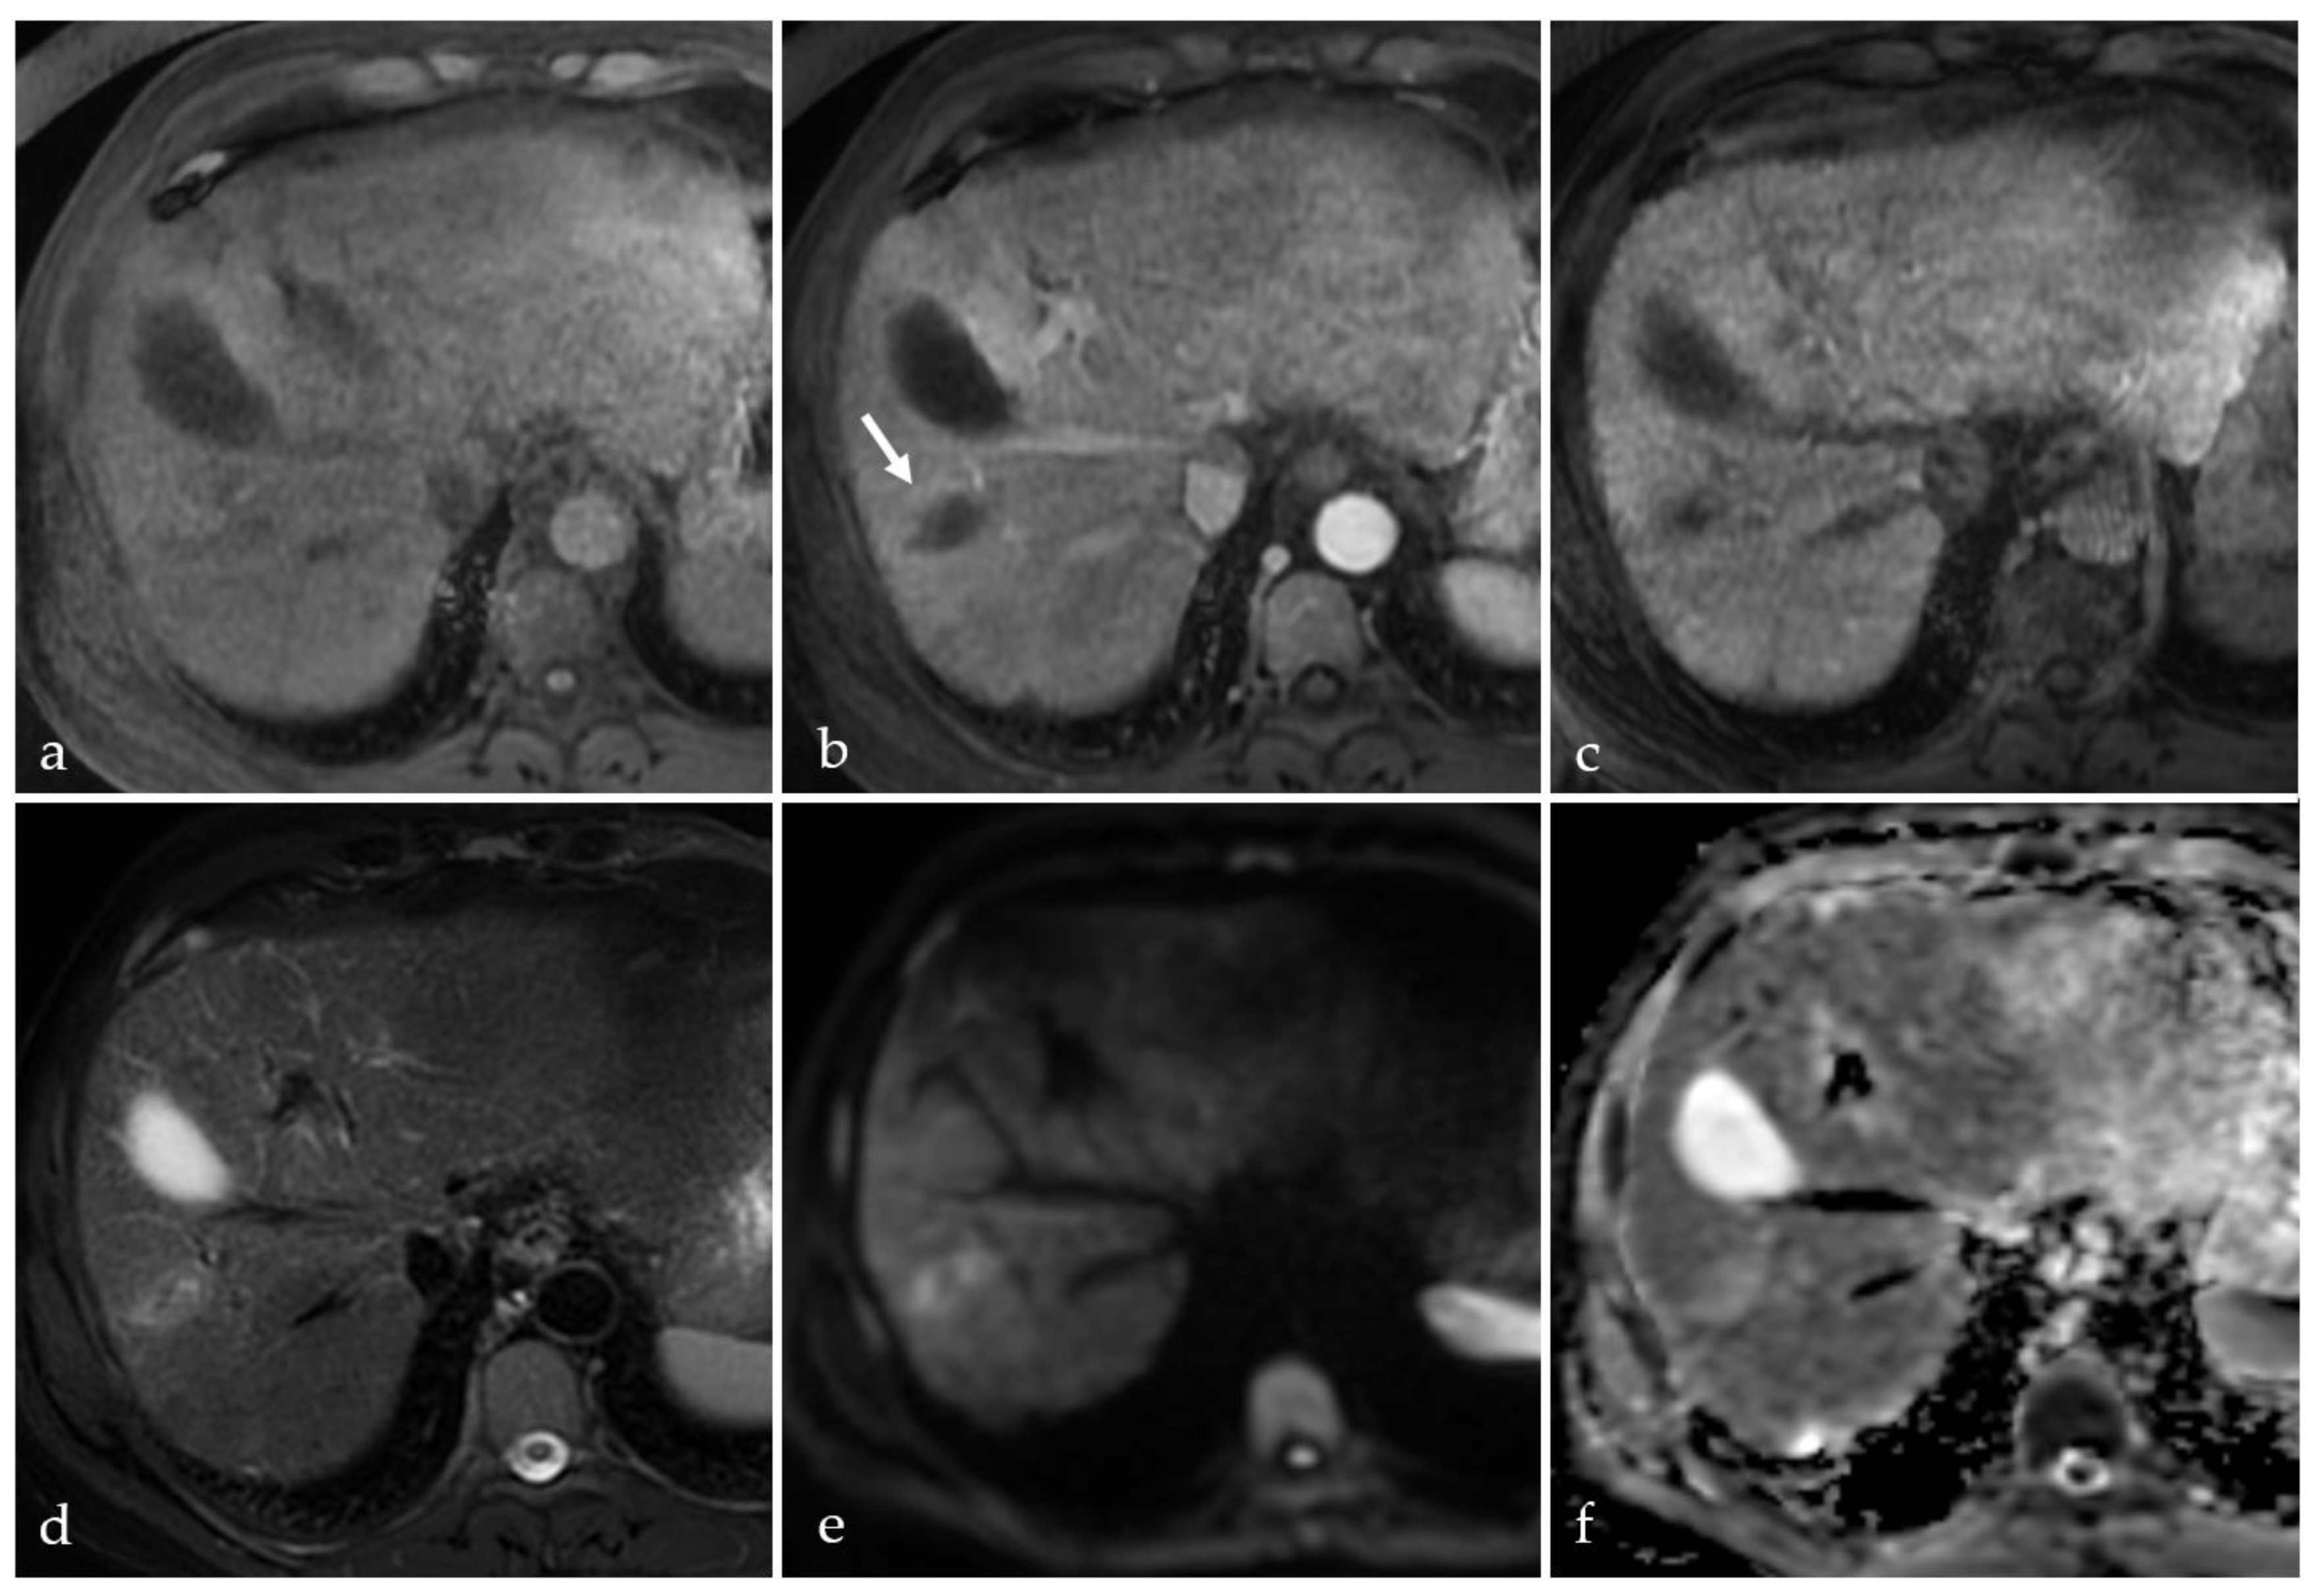

3.4. TACE-Associated Necrosis

3.5. Post-Treatment Imaging Features of Tumor Viability